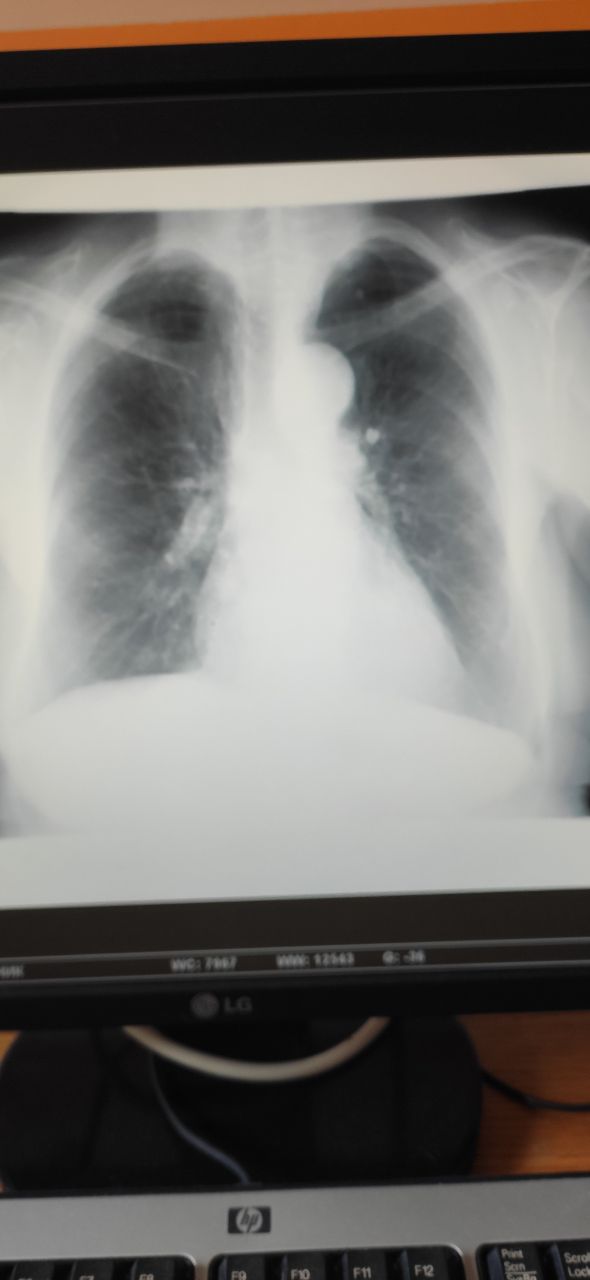

Женщина, 83 года, проф осмотр, слева это пневмония или такое сгущение за счёт плохого вдоха?

Сложно сказать, тучный пациент, плюс рентген на выдохе вероятно. Врятли что пневмония.

Фаза вдоха разная

Как то размеры сердца разные ну и в базальных не спокойно

Интересно, что это может быть. Необычная структура тени, как будто ткань пропитанная

Картина может очень заметно отличается на вдохе и на выдохе. Сам когда то попал в эту ловушку😔

Стоит ещё с небольшим разворотом, за счёт этого плотность легкого слева кажется больше. Если смущают базальные отделы, делайте боковушку.